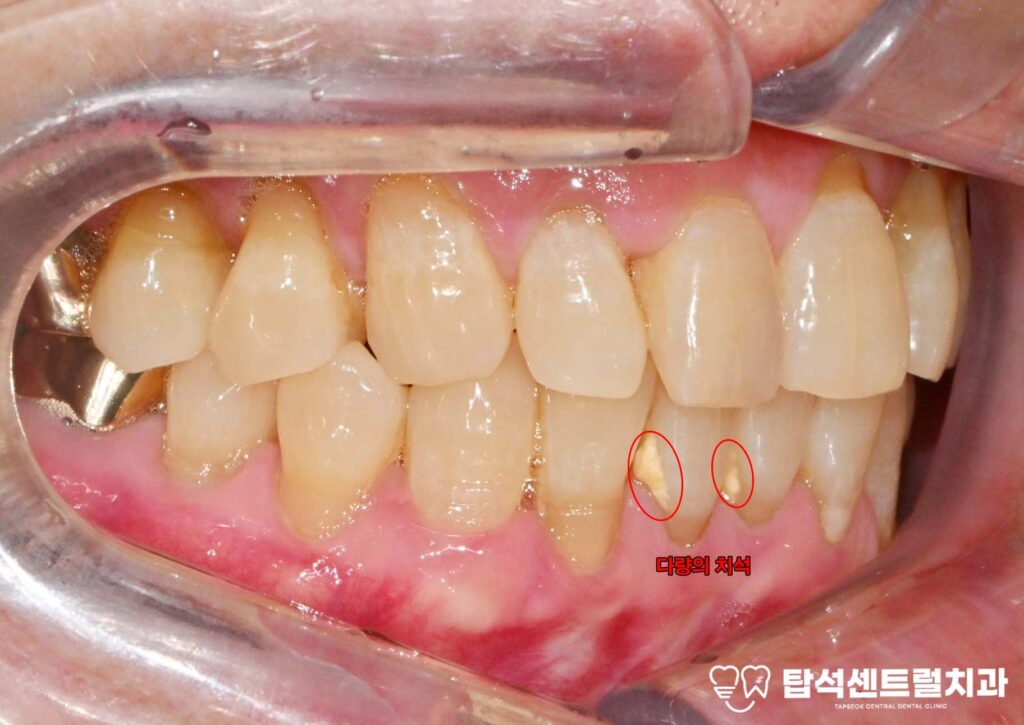

교합 관계가 맞지 않거나

잇몸 질환으로 인해

치조골이 약해진 경우에도

이가 이동하면서

공간이 발생하기도 합니다.

치아 사이에 음식물이 자주 끼어

잇몸 염증과 충치가 발생할

위험이 높아지며,